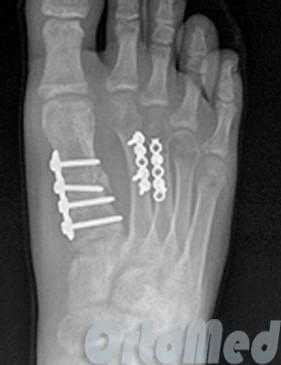

Открытая репозиция перелома

Открытая репозиция при переломе плюсневой кости стопы, накостный остеосинтез пластиной и винтами. Операция включает в себя хирургический разрез, доступ к сломанной плюсневой кости аккуратно отводя сухожилия, сосуды и нервы, мобилизацию костных отломков, устранение смещения и фиксация в правильном положении.

Гипсовая иммобилизация не проводится, так как металлоконструкция, фиксирует отломки.

Разрешается ходьба с опорой на пяточную область в течение месяца.

Это возможно благодаря множеству поперечных связок, выполняющих роль стабилизаторов отломков, благодаря шинированию с неповреждёнными плюсневыми костями. При повреждении более чем одной плюсневой кости, значимом смещении (более 4 мм), методом выбора становится оперативное лечение. Для оперативного лечения могут использоваться как вводимые интрамедуллярно спицы, винты или стержни (в случае ротационно относительно стабильных переломов), так и минипластины (как компрессирующие так и блокируемые) или же использование компрессирующих винтов (2-3) без пластины. В послеоперационном периоде требуется ходьба в ортезе без нагрузки до появления признаков консолидации.

Для остеосинтеза чаще всего используются компрессирующие винты и пластины.